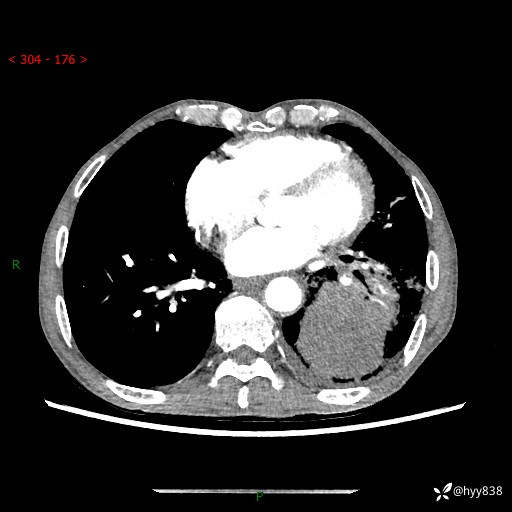

77岁/男,腹痛2月,CT发现左肺占位1天。巨大肿块,肺内或肺外来源…结果公布~

主诉:腹痛2月,CT发现左肺占位1天

现病史:患者于2025年9月间断左下腹胀痛,在当地镇卫生院行彩超检查考虑泌尿系结石,行止痛排石对症治疗未见明显好转;1天前腹痛症状加重,至当地市第三人民医院行CT检查:左肺下叶巨大团块状软组织影,考虑肿瘤性病变,建议增强CT检查;左侧胸腔积液;纵膈内淋巴结肿大;双肺肺气肿;右肺中叶纤维灶。为进一步求治,来我院就诊。

胸部CT平扫+增强